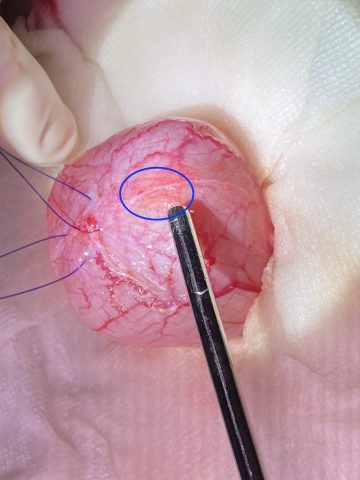

お腹を開け、膀胱周囲にガーゼを敷き詰め(膀胱移行上皮癌は、播種といって尿がお腹の中に漏れ出るとそこに癌が発生する可能性があるため、尿を漏らさないように細心の注意を払う必要があります)、エコー検査で腫瘍の位置を再確認しました(青丸が腫瘍が存在する位置です)。

腫瘍から1cmほど離れた正常な膀胱に切開を加え、腫瘍を触らないように膀胱を切除しました(青丸が腫瘍です)。